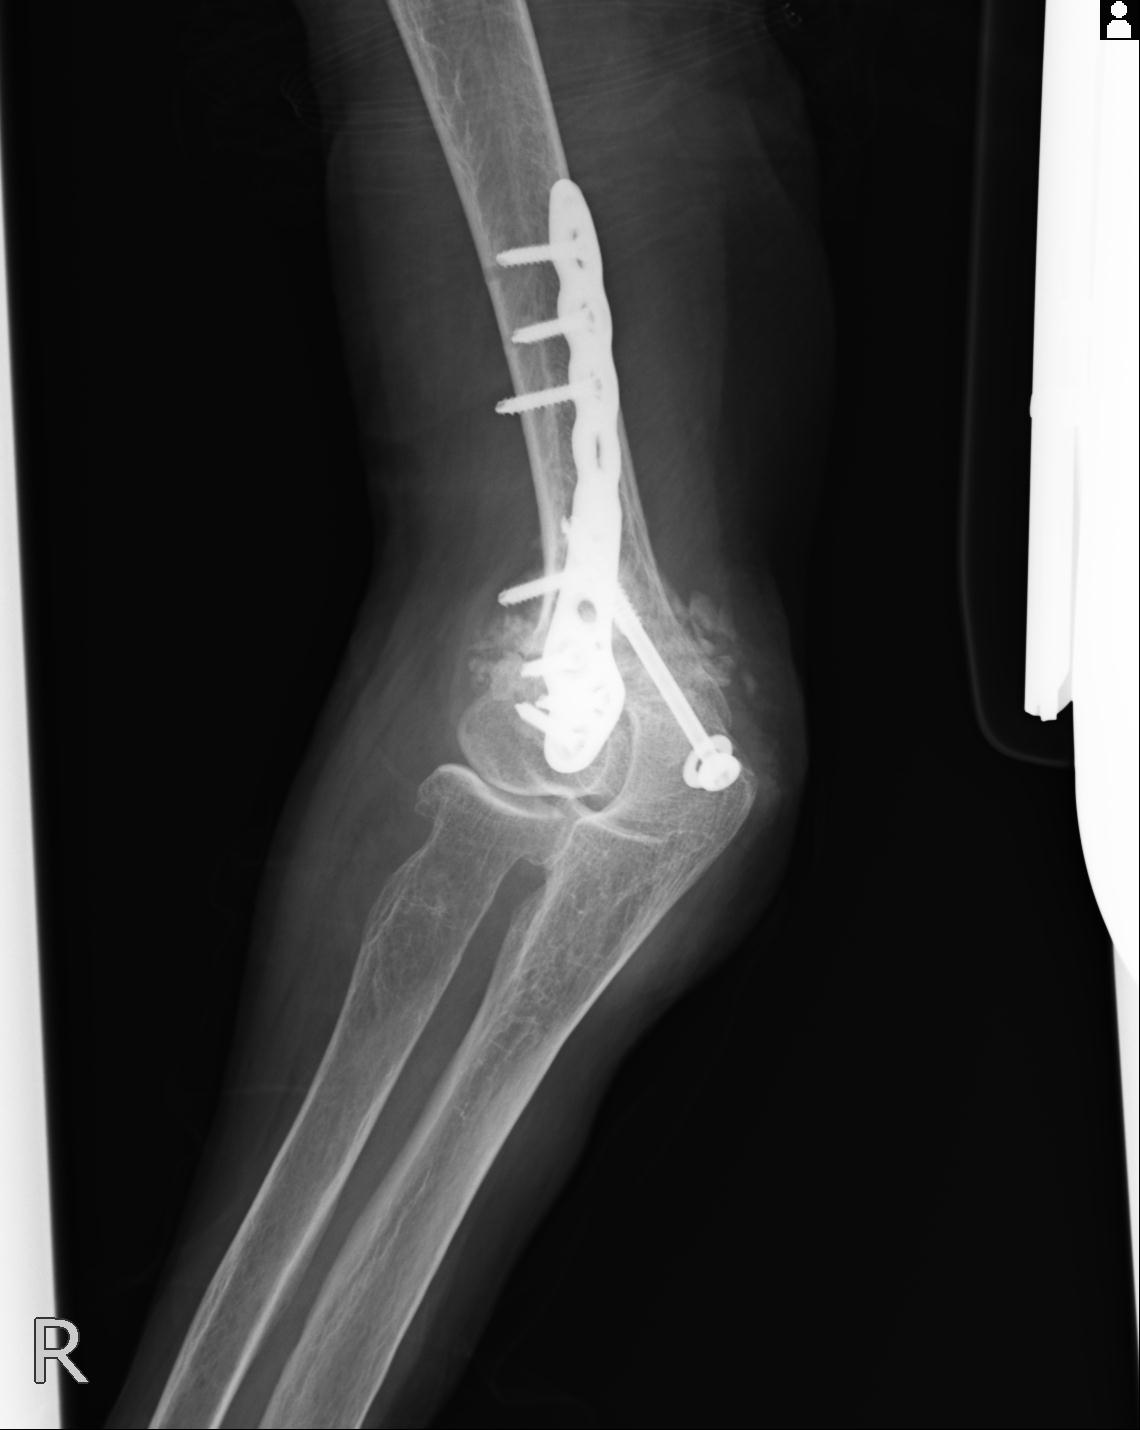

2271 1/25 右肘 4R 1/27 4R 3/24 4R 94歳女性 右通顆骨折